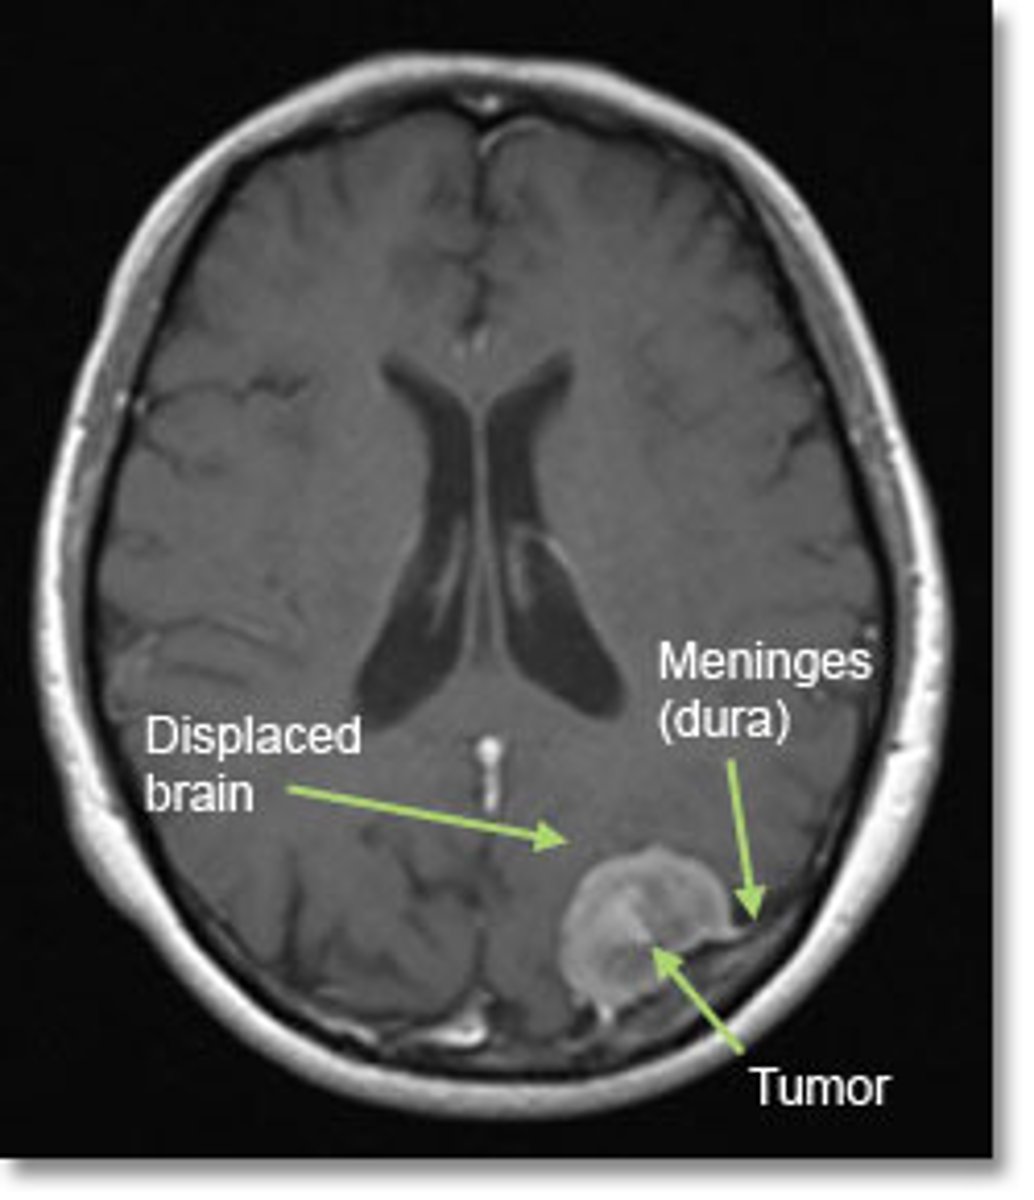

meningioma

benign tumor of the coverings of the brain (the meninges). Most common CNS tumor